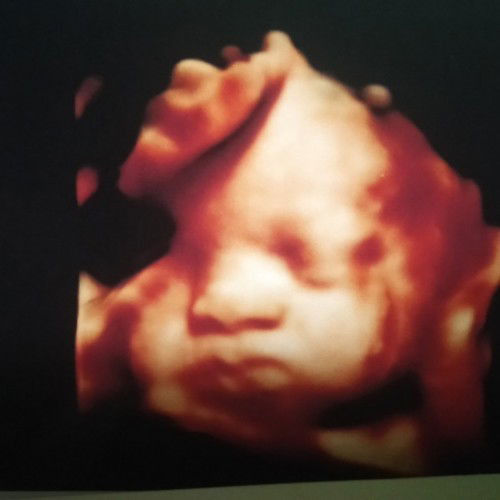

Bun mau sedikit cerita.kandungan sya skrang 35 week 3 hari.tdi sya usg dan kepala si urun msih di atas.dn dokter nyruh buat USG lgi 2 mnggu lgi.dn klau posisi msih sma dokter skalian mau nntuin kpan buat oprasi nya.doa in ya Bun..smga si urun cpet muter kebwah dan masuk panggul#bantusharing